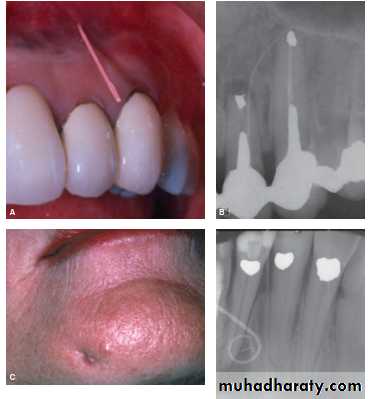

Chronic Apical Abscess

A chronic apical abscess is characterized by the presence of a draining sinus either intra-orally or extra-orally on the the condition may oscillate between being chronic

apical periodontitis and a chronic apical abscess.

Typical symptoms—usually there are no symptoms; some

patients may be aware of the presence of a draining

sinus (they may refer to it as a “gum boil,” “lump,”

“ulcer,” etc.); the draining sinus is usually intra-oral (on

the oral mucosa) but may be extra-oral (on the face);

Clinical findings—may be caries, a restoration breaking

down or a crack; the tooth is not tender to percussion;

may feel “different” to percussion; no response to pulp

sensibility tests; draining sinus evident—intra-oral or

extra-oral; palpation or pressure on the tissues overly-

ing the periapical region may cause pus to exude from

the draining sinus; can often insert a gutta-percha point

into the draining sinus to trace it radiographically.

Radiographic findings—caries may be seen if extensive

enough; there is a periapical radiolucency present; a

gutta-percha point inserted into the draining sinus can

trace its origin to the infected tooth; some cases may

have evidence of previous endodontic treatment; occa-

sionally may see a radiolucency within the tooth root

indicating internal inflammatory resorption.

Key findings for diagnosis—there is a draining sinus, a periapical

radiolucency and no pain or only occasional “awareness.”

Distinguish from chronic apical periodontitis by the presence of the draining sinus.